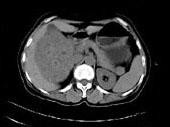

女,57岁,右腰部胀痛6月余,触及右侧腹部包块2月,CT平扫及增强如图所示,下列说法正确的是?(?)

• A.平扫时可见右侧腹部巨大的软组织肿块影,其内可见小片状的低密度影

• B.增强扫描肿块强化明显,其内可见无强化的低密度坏死灶

• C.考虑肿块来源于肝脏,是原发性肝癌,并挤压推移右肾

• D.考虑肿块来源于右肾,是巨大的肾癌,并挤压推移右肝,与其分界欠清

• E.考虑肿块来源于右肾,是肾血管平滑肌脂肪瘤,并挤压推移右肝,与其分界欠清